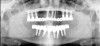

Figure 13  Radiograph depicting the necessity of horizontal placement parameters to prevent vertical defects from becoming horizontal defects.

Figure 13